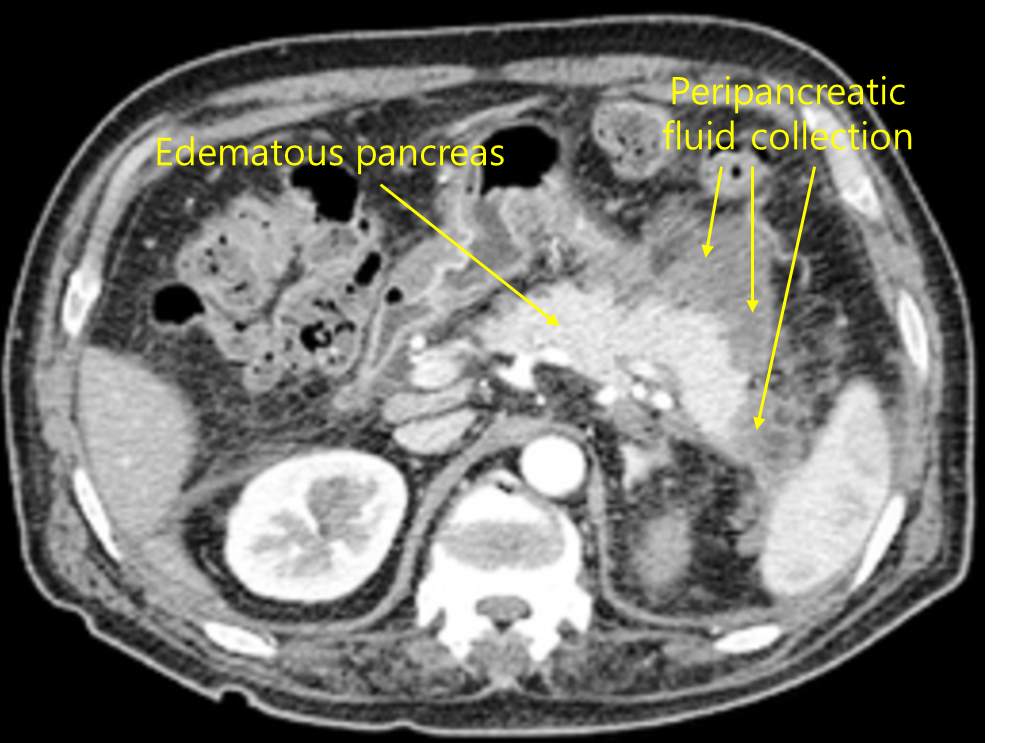

51세 여자가 2일 전부터 배가 아파서 왔다. 통증은 상복부와 등쪽으로 뻗치고 누워 있으면 더 심해져 거의 앉아서 허리를 숙이고 지냈다고 하였다. 하루 6번 구토를 하였다. 3년 전에 고혈압과 이상지질혈증을 진단받았고 음주력은 없었다. 혈압 120/80mmHg, 맥박 96회/분, 호흡 20회/분, 체온 37.2℃였다. 복부 청진에서 장음은 들리지 않았다. 윗배에 압통이 있었고 덩이는 만져지지 않았다. 혈액검사 결과는 다음과 같았다. 복부 컴퓨터단층촬영 사진이다. 적합한 조치를 고르시오 (두 가지).

백혈구 8,800/mm3, 혈색소 14.6g/dL, 혈소판 180,000/mm3, 총빌리루빈 1.2mg/dL, 아스파르테이트아미노전달효소 86U/L, 알라닌아미노전달효소 72U/L, 알칼리인산분해효소 100U/L, 포도당 136mg/dL, 중성지방 960mg/dL, 아밀라아제 662U/L, 리파아제 452U/L, 혈액요소질소/크레아티닌 24/1.4mg/dL, C-반응단백질 120mg/L(참고치, <10), 암항원(CA) 19-9 4.2U/mL(참고치, <37)

Img | CT: 췌장 종대, fluid collection |

• 등쪽으로 방사되는 상복부 통증, 누우면 악화되고 허리를 숙이면 완화되는 통증, 동반된 구토 증상, 혈액검사 상 amylase와 lipase의 상승은 급성 췌장염을 의심할 수 있는 소견이다. 환자의 hypertriglyceridemia를 원인으로 추정할 수 있다. 복부 CT에서 췌장 종대와 fluid collection이 관찰되므로 급성 췌장염을 진단할 수 있다.

진단 | • US: 담석, 담관확장 확인 • CT: 췌장 실질의 edema, 췌장 근처 조직의 inflammation |